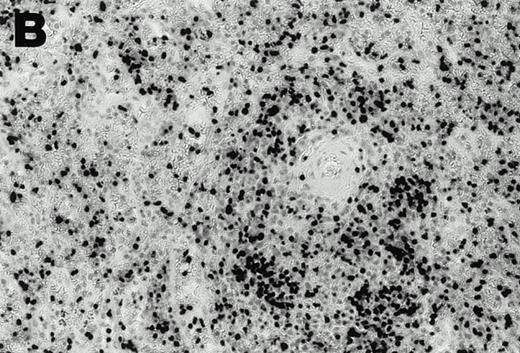

Lymphomas were diagnosed in the lymph node from patient 1 and in the spleen from patient 2 at 19 months and 3 months, respectively, after peripheral blood CD4+ T-cell infection with EBV was documented. Both lymphomas were EBV positive by EBER1 in situ hybridization (Fig 2), and were of T-cell lineage as determined by immunohistochemistry with an anti-CD45RO and anti-CD4 MoAb, and Southern analysis that detected rearranged T-cell receptor γ- and β-chain genes with germline immunoglobulin JH genes (not shown).

Detection of EBER1 expression by in situ hybridization of lymphoma tissues. (A) Lymph node from case 1 (100X magnification); (B) spleen from case 2 (200X magnification).